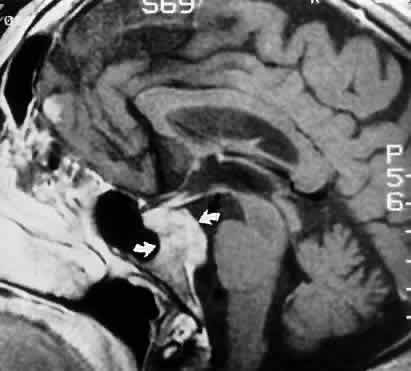

When associated orbital and cranial signs and symptoms are absent, and when laboratory and appropriate radiologic studies are normal, the most prudent and practical course to follow is continued observation. An examination by a neurologist is comforting, but even Tensilon testing may be postponed. In this specific clinical situation, neuroimaging is infrequently productive, and its application in the elucidation of acute or subacute isolated sixth nerve palsies is moot. However, further radiologic evaluation must be undertaken if pain persists or develops, if other cranial nerves become involved, or if the palsy does not begin to improve over a 3- to 4-month period. Although it is true that some isolated “chronic” sixth nerve pareses last longer than 6 months, yet follow a completely benign course,25 others are indeed caused by potentially treatable basal tumors.26 Volpe and Lessell27 reported seven patients with relapsing or remitting sixth nerve palsies, which were ultimately identified to be secondary to extramedullary compression of the abducens nerve by skull-based tumors. No patients had diabetes or vascular disease, and all recovered completely at least once (and in one case in five separate episodes) without surgical intervention, radiotherapy, or chemotherapy before a definitive diagnosis was made. Lesions included chordomas (Fig. 8), chondrosarcomas, and presumed meningiomas.

Fig. 8. MRI sagittal section, gadolinium enhanced, shows clivus chordoma (arrows). Patient presented with chronic bilateral sixth nerve palsies.